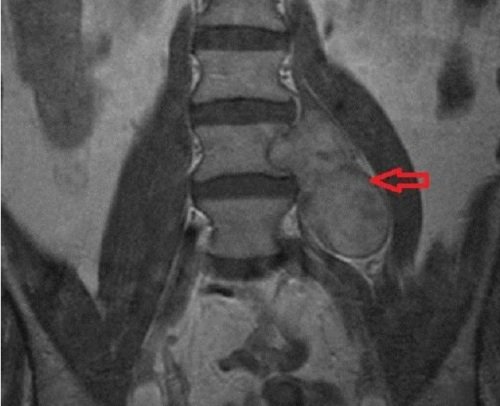

- Шваннома позвоночника. Может располагаться в грудном отделе или шее, редко – в поясничном отделе, и является раком на спинномозговых нервных окончаниях. Эта опухоль самая распространенная. Развивается она как экстрамедуллярно-интрадуральная в шванновских клетках. Такого типа образования могут проникать сквозь межпозвонковые отверстия экстродурально (это свойственно шейным невриномам). Подобный вид невриномы можно отнести к типу «песочных часов» и типичен для шейного отдела. Из-за позвоночных шванном могут развиться костные деформации, которые обнаруживаются с помощью спондилографической диагностики (спондилографии);

- МРТ, которое позволяет визуализировать шванномы на начальных этапах их формирования;

- КТ, при наличии контрастного вещества, что позволяет диагностировать опухоли незначительного размера;